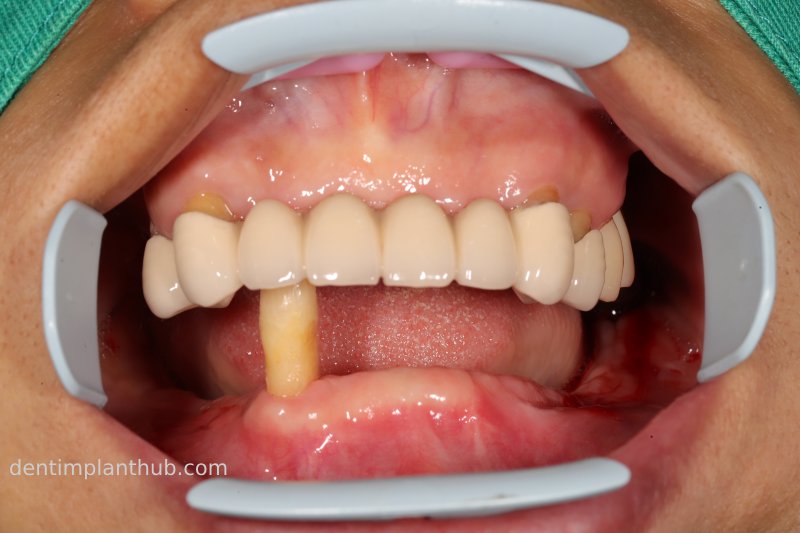

7/6/24 Mandibular preparation for wearing a fixed prosthesis supported by a maroon bridge

Intraoral photographs after putting it on

Photo of temporary crown worn into the mouth on the day of surgery, 7 June '24

A fixed prosthesis supported by a Marrowbridge will be worn in the coming months, and the case will be completed at that time.